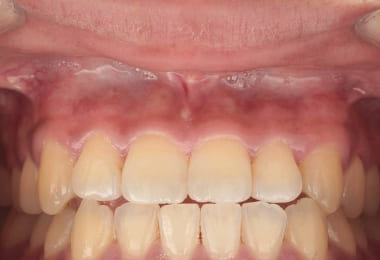

Before

1週間後

After